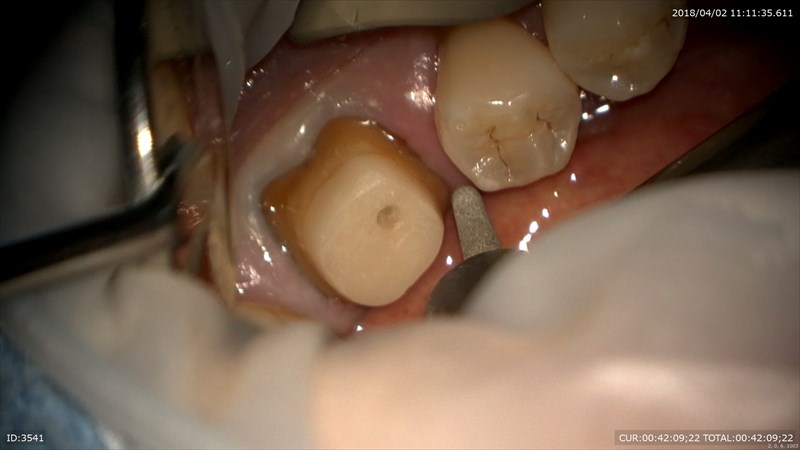

型取りは非常に大切で最も難しいと感じる今日この頃。1ケースご紹介。左下の根管治療が終わり土台を立て歯周組織の安定が図れた状態でしたので本日最終的な型を取りました。

担当している技工士間中さんは妥協を許さない人。だから良い仕事が出来る。何回でも突き返してきます。笑。特に難しいのはこの歯茎と歯の境目をしっかり出すこと。歯茎の厚みなどを考慮して糸を変えます。

このままで型を取ると歯根の立ち上がりが全く分かりません。

だからこのように1本糸を差し込み